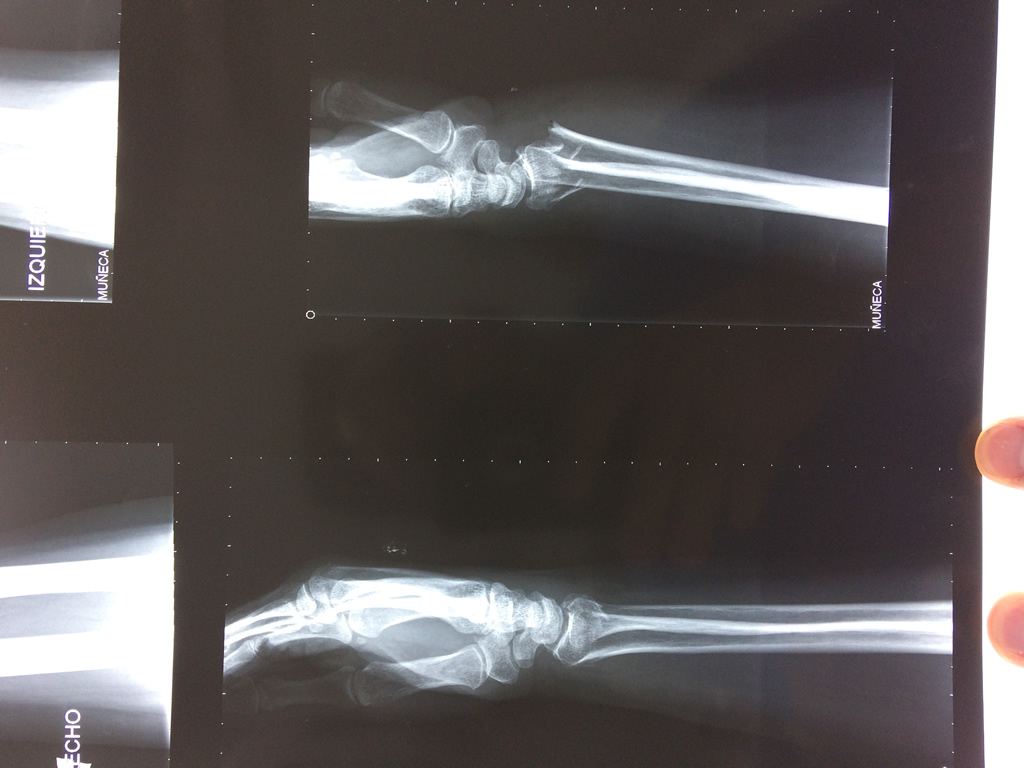

Cirugías de Codos - Cirugías de Muñecas y Manos

Los procedimientos más comunes en cirugía de la mano son aquellos destinados a reparar traumatismos, incluyendo lesiones de tendones, nervios, vasos sanguíneos, y articulaciones; huesos fracturados; y quemaduras, cortes, y otros daños de la piel.